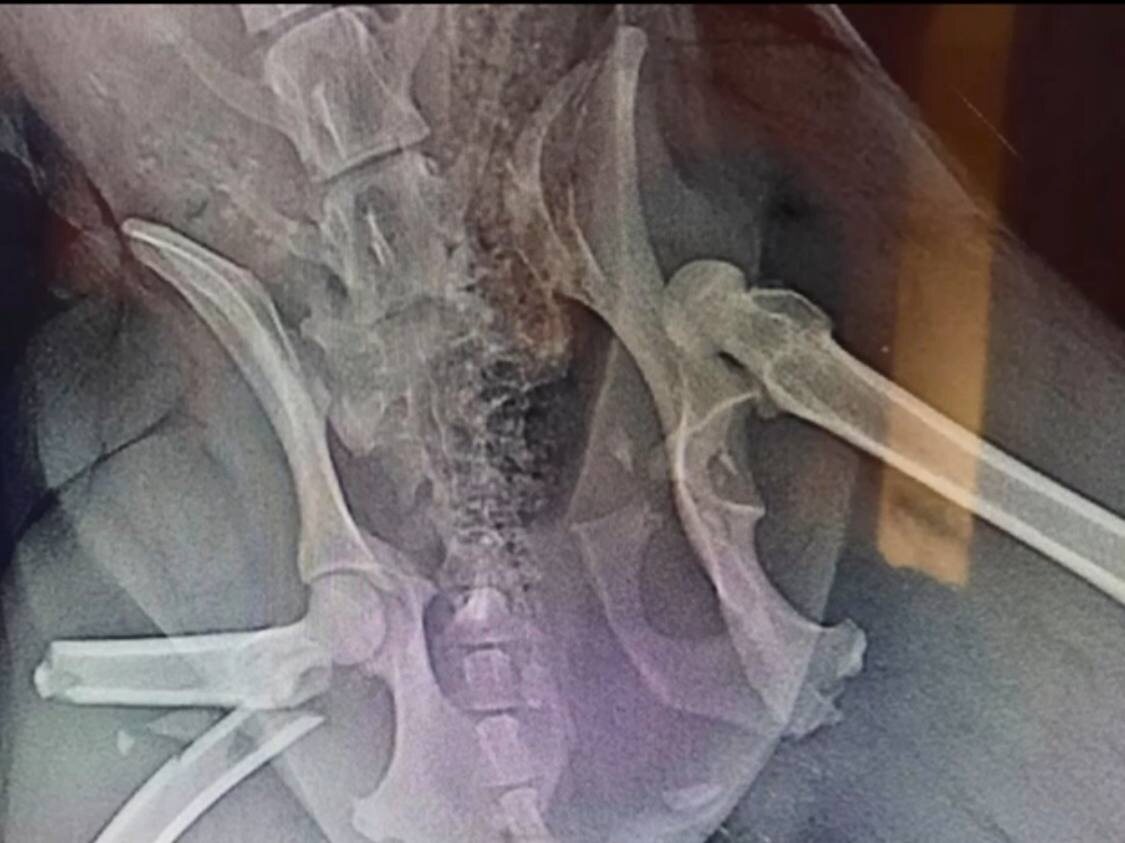

- У Джессики очень серьёзные травмы костей: вывих левого бедра, перелом правой бедренной и подвздошной кости, грыжа, - уточнили волонтеры. - Повезло, что она осталась жива в этот раз.

Джессика лежала на обочине дороги. Собаку сбили и бросили умирать с серьезными травмами.